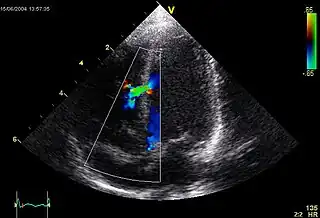

![]() Imagen ecocardiográfica de una comunicación interventricular moderada en la parte media muscular del septo interventricular. El trazado en la parte inferior izquierda muestra el flujo durante un ciclo cardíaco completo y la marca roja el momento del ciclo cardíaco en el que la imagen fue capturada. Los colores representan la velocidad del flujo sanguíneo. El flujo va desde el ventrículo derecho al ventrículo izquierdo (a la izquierda de la imagen). El tamaño y la posición es típica de una CIV en el período neonatal. | ||